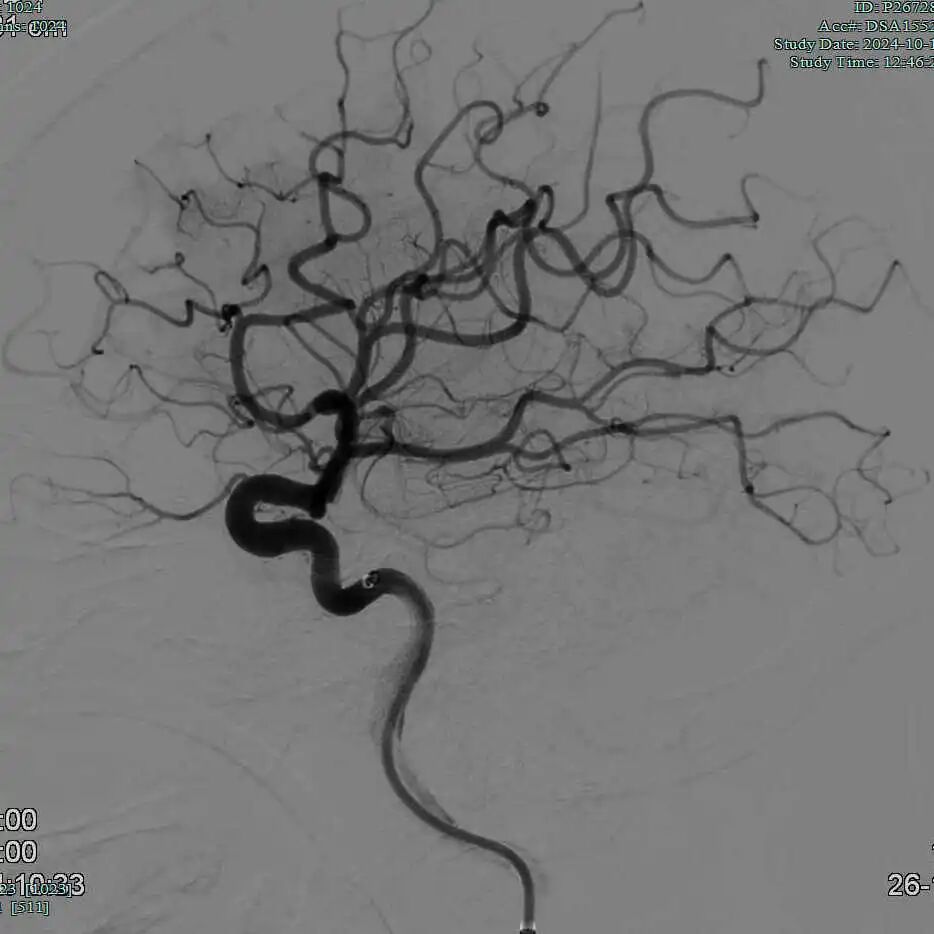

90cm Locaste 088输送导管建立路径,造影提示左侧大脑中动脉M1段闭塞。

动脉长鞘怎么置入有励可说|Locaste 088励楷长鞘及Tarvos微导丝在左侧大脑中动脉闭塞取栓术中的应用_https://www.jmylbn.com_新闻资讯_第8张

动脉长鞘怎么置入有励可说|Locaste 088励楷长鞘及Tarvos微导丝在左侧大脑中动脉闭塞取栓术中的应用_https://www.jmylbn.com_新闻资讯_第9张

动脉长鞘怎么置入有励可说|Locaste 088励楷长鞘及Tarvos微导丝在左侧大脑中动脉闭塞取栓术中的应用_https://www.jmylbn.com_新闻资讯_第10张